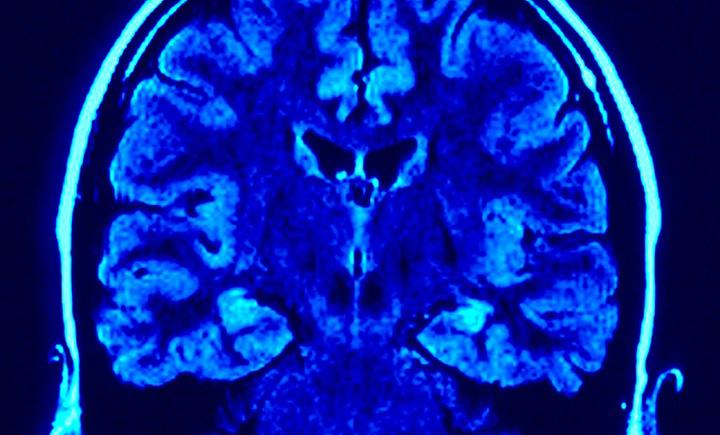

Serviços de saúde têm de adaptar-se a nova realidade de doentes de Parkinson

O neurologista Joaquim Ferreira defendeu ontem que os serviços e os profissionais de saúde têm de adaptar-se para responder às necessidades dos doentes de Parkinson com abordagens terapêuticas mais multidisciplinares e integradas.